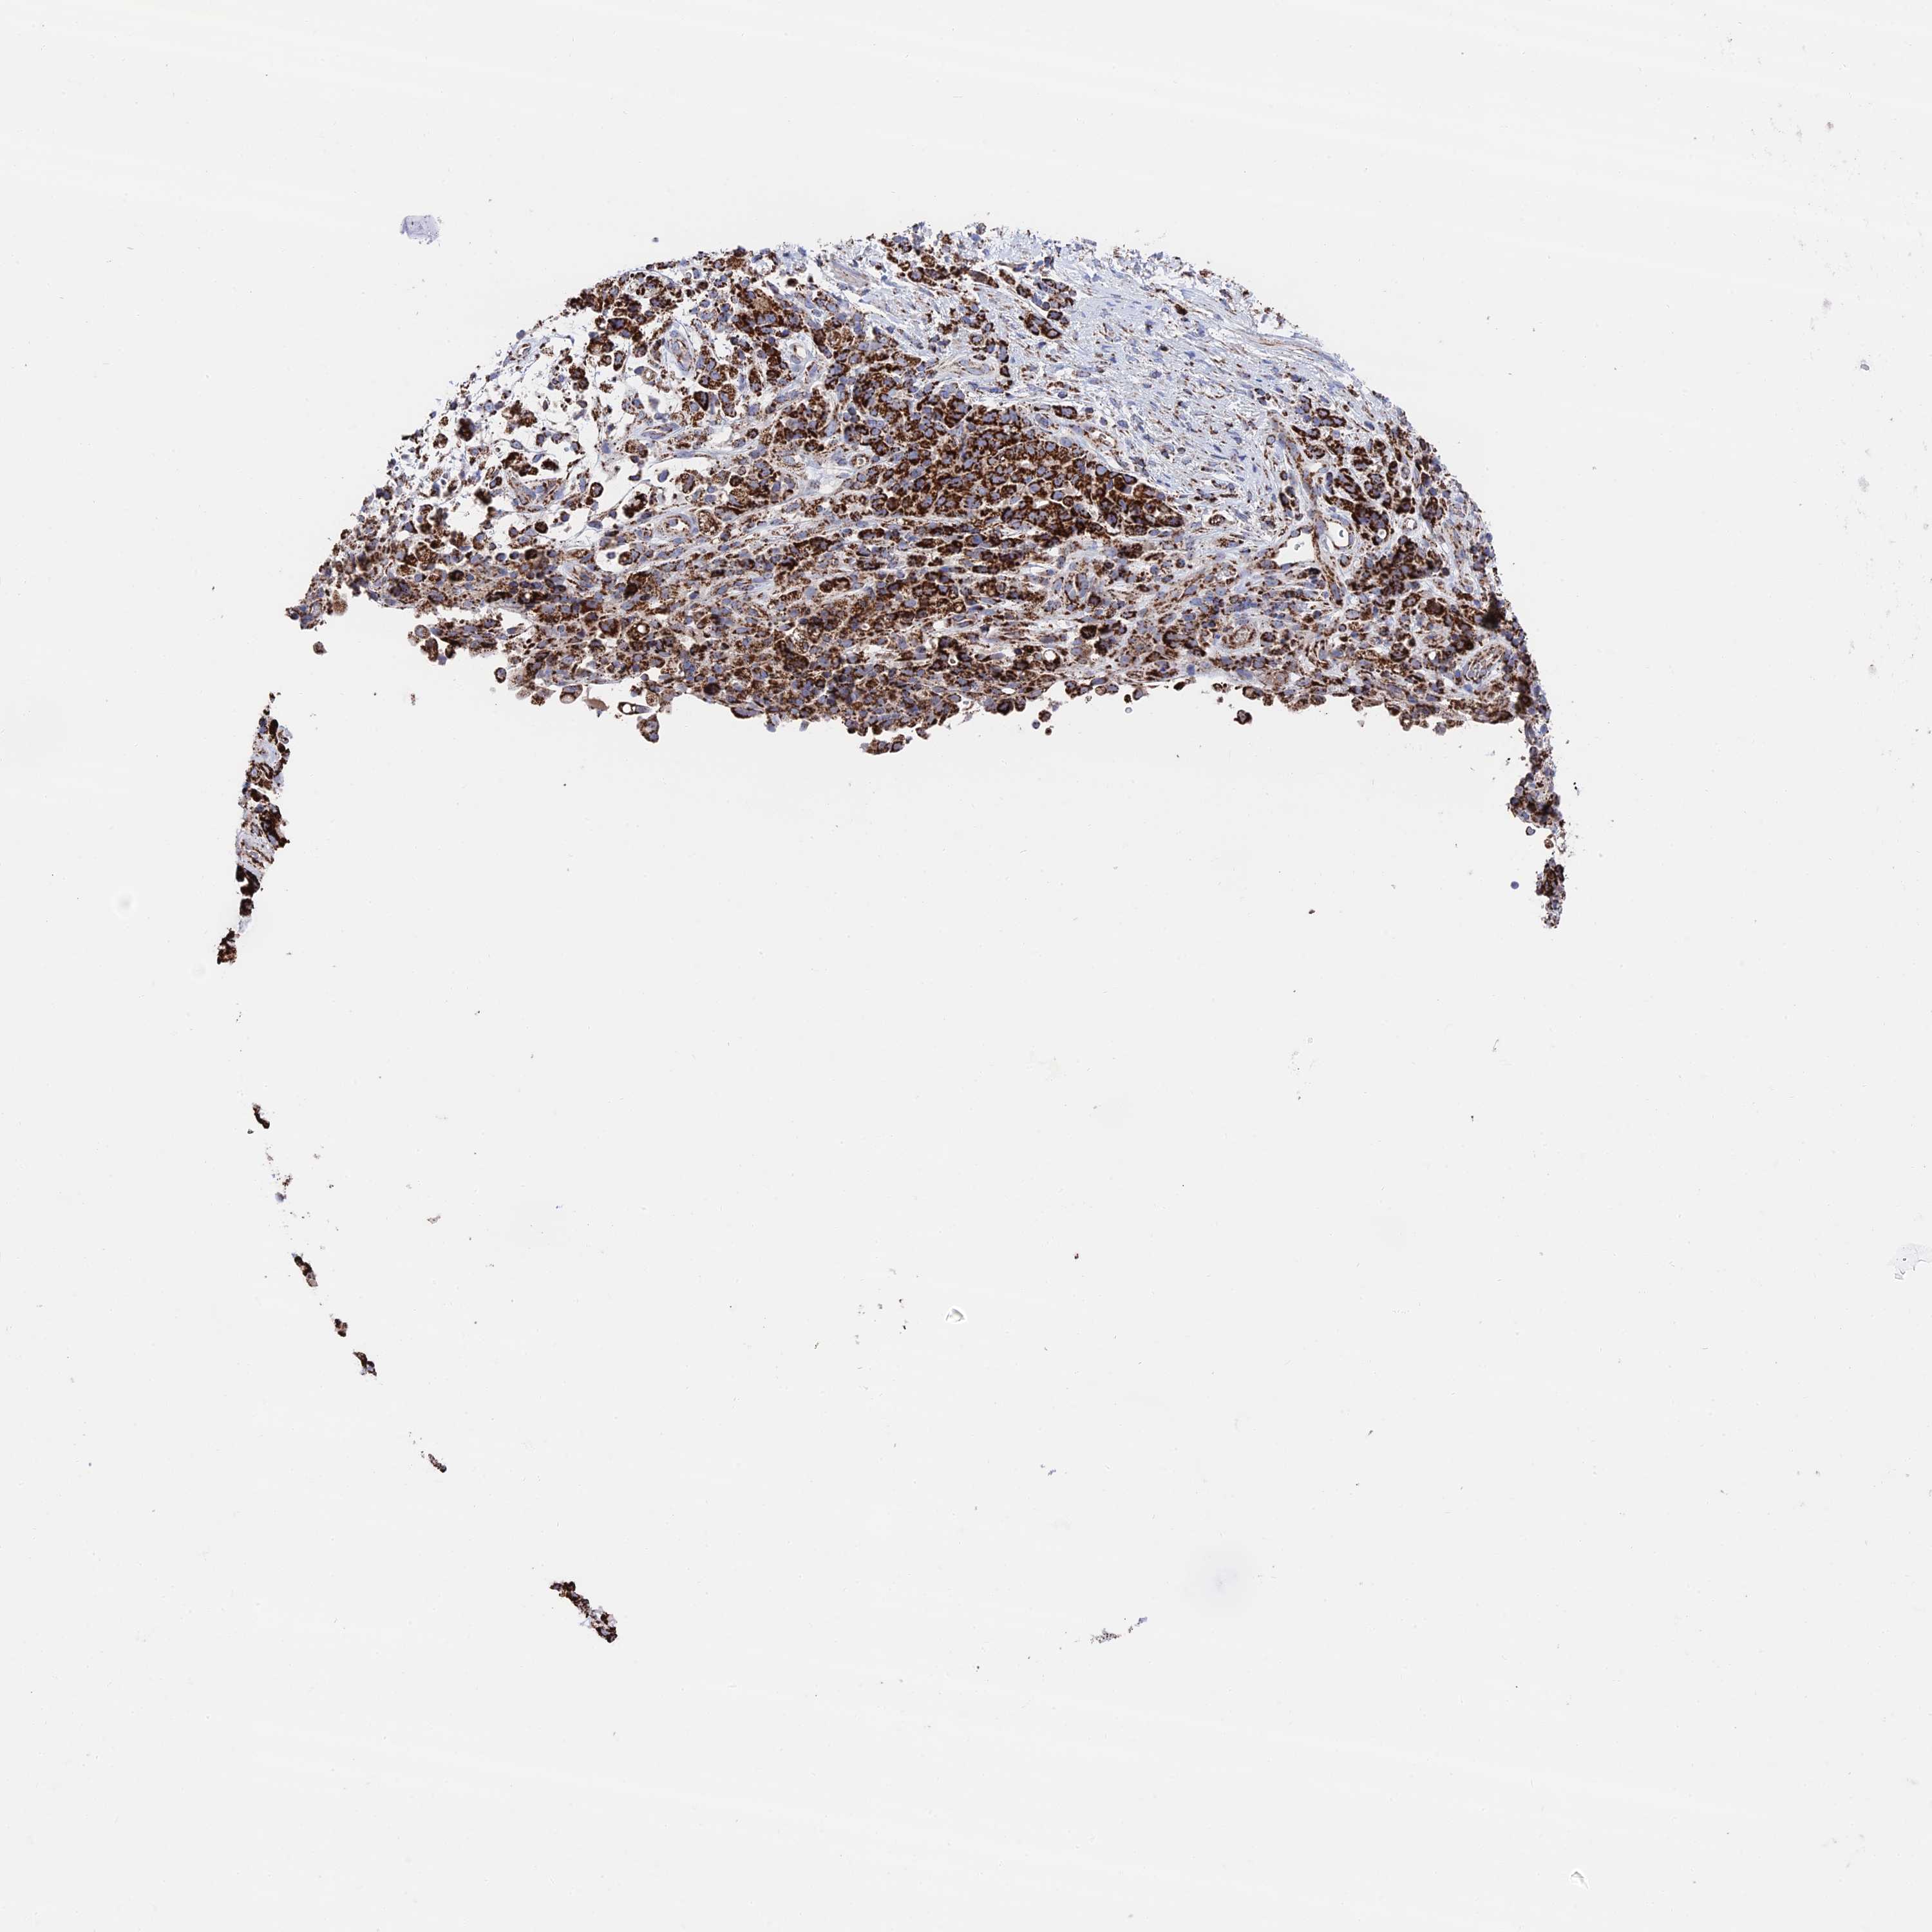

STOMACH CANCER - Protein expressioni

A mouse-over function shows sample information and annotation data. Click on an image to view it in a full screen mode. Samples can be filtered based on level of antibody staining by selecting one or several of the following categories: high, medium, low and not detected. The assay and annotation is described here.

Note that samples used for immunohistochemistry by the Human Protein Atlas do not correspond to samples in the TCGA dataset.

Antibody stainingi

Antibody staining in the annotated cell types in the current human tissue is reported as not detected, low, medium, or high, based on conventional immunohistochemistry profiling in selected tissues. This score is based on the combination of the staining intensity and fraction of stained cells.

Each image is clickable and will lead to virtual microscopy that enables deeper exploration of all samples and also displays staining intensity scores, fraction scores and subcellular localization as well as patient and tissue information for each sample.

Antibody HPA039406

Staining

High

Medium

Low

Not detected

Intensity

Strong

Moderate

Weak

Negative

Quantity

>75%

75%-25%

<25%

None

Location

Nuclear

Cytoplasmic/membranous

Cytoplasmic/membranous,nuclear

Adenocarcinoma, NOS